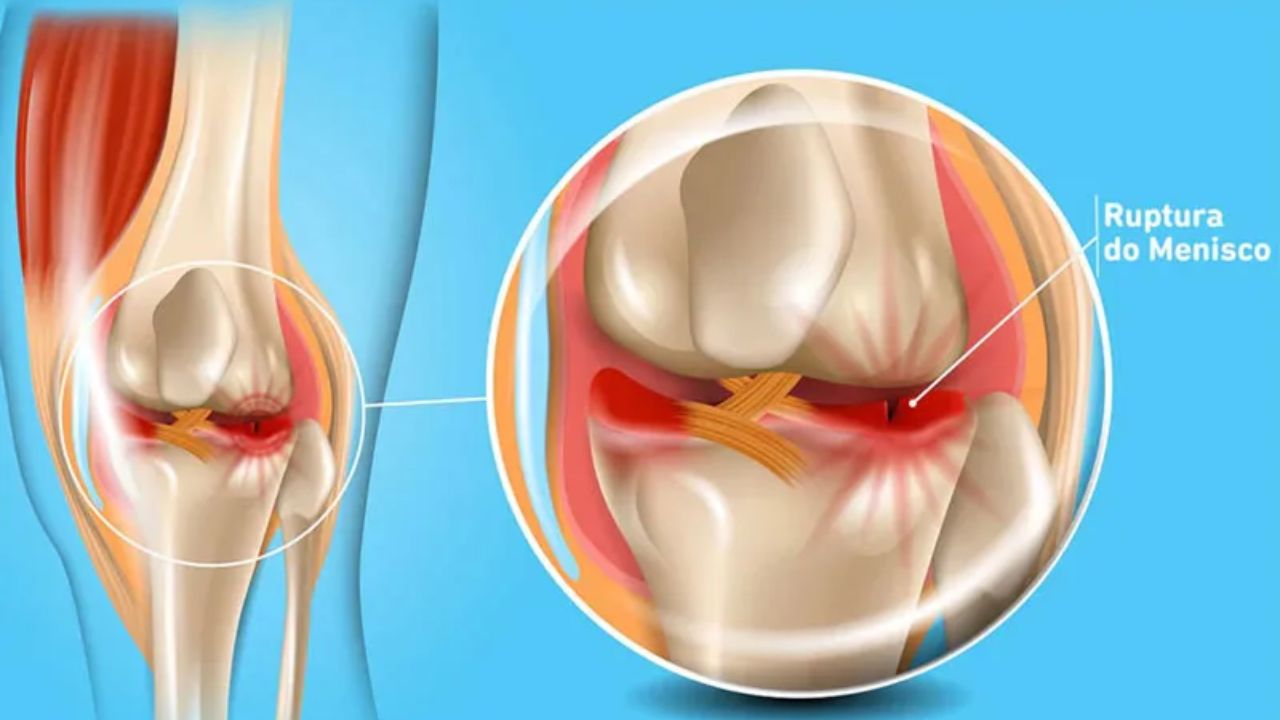

Lesão de Menisco Agendar consulta A lesão de menisco é uma das causas mais frequentes de dor no joelho, afetando tanto atletas quanto não atletas.